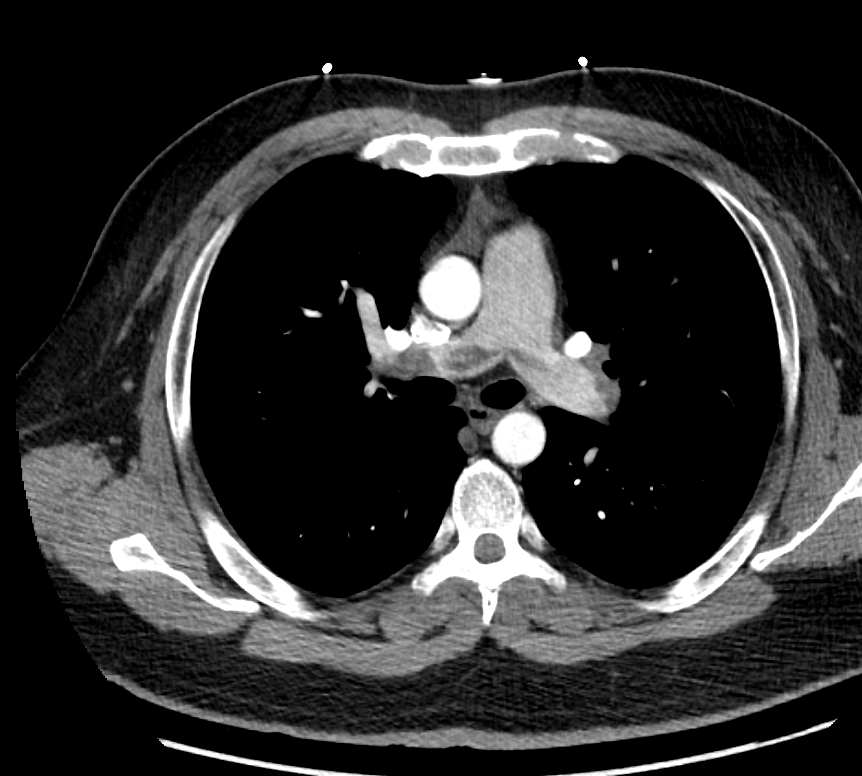

Repeat CTA (poor contrast bolus timing) persistent saddle PE

! Anyone has seen this? Despite tPA. persistent RVdilated reason for above EKG! @Yalecards @infeldMD @turilrh @jedicath @mirvatalasnag @jgloyo @PowellJose @karimratib @KHERA_MD @RealKushAgrawal @shiskumar33 @samikhan0